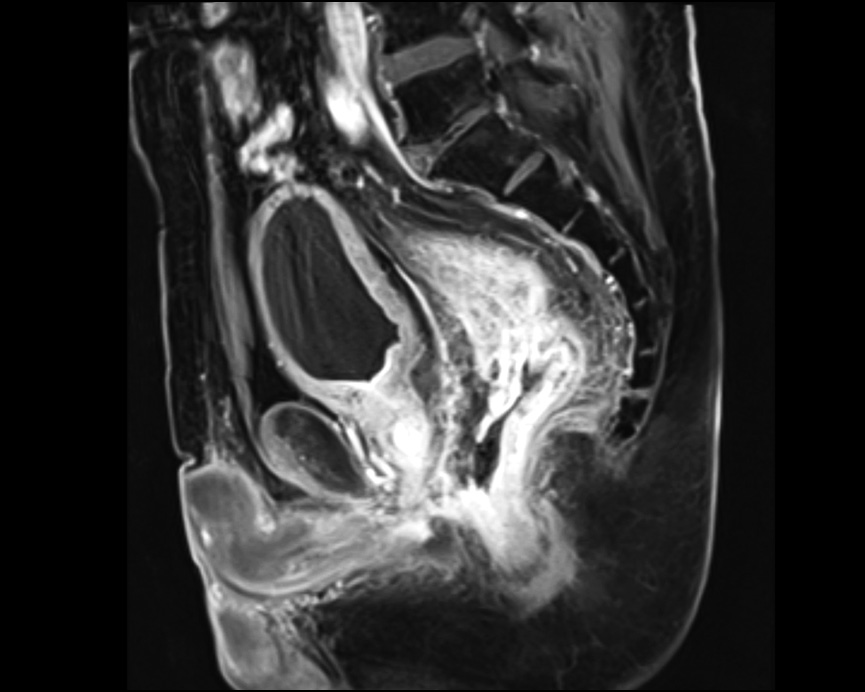

Рис. 5. Магнитно-резонансная томография малого таза: диффузное утолщение стенки прямой кишки с сужением просвета, реактивный отёк мезоректальной клетчатки; веретеновидный затёк диаметром 10 × 15 мм протяжённостью 45 мм, распространяющийся в воспалительном инфильтрате вдоль передней стенки кишки

Через неделю после второй процедуры аргоноплазменной коагуляции пациента начали беспокоить абдоминальный болевой синдром, боли в области заднего прохода, появилась примесь крови в стуле. При контрольном эндоскопическом исследовании по передней стенке прямой кишки выявлены некротизированные массы (рис. 4). При магнитно-резонансной томографии малого таза стенки прямой кишки диффузно утолщены с сужением просвета кишки, реактивным отёком мезоректальной клетчатки; на расстоянии 4,3 см от анального края передняя стенка кишки изъязвлена на протяжении 2,3 см; на уровне изъязвления на 12−13 часах веретеновидный затёк диаметром 10 × 15 мм протяжённостью 45 мм, распространяющийся в воспалительном инфильтрате вдоль передней стенки кишки (рис. 5), верхняя граница затёка на уровне S5; стенка сигмовидной кишки без признаков воспалительных изменений; тазовой лимфаденопатии не выявлено. Предстательная железа размерами 44 × 37 × 29 мм, объём 25 см3. Строма простаты диффузно отёчная, наружный контур простаты на 15−18 часах нечёткий, в структуре паренхимы визуализируются гипоинтенсивные частицы. Клетчатка ректопростатических углов не изменена. Семенные пузырьки симметричные, малых размеров. Мочевой пузырь умеренно наполнен, стенки циркулярно утолщены до 6−7 мм, внутренний контур повышенной трабекулярности. Тазовые сегменты

мочеточников не расширены, содержимое пузыря без особенностей. Кости таза без патологических инфильтратов.

Заключение: Состояние после ЛТ предстательной железы, посттерапевтические изменения паренхимы железы. Постлучевой проктит, осложнённый изъязвлением передней стенки прямой кишки, парапроктитом с формирующимся абсцессом. Постлучевой цистит.